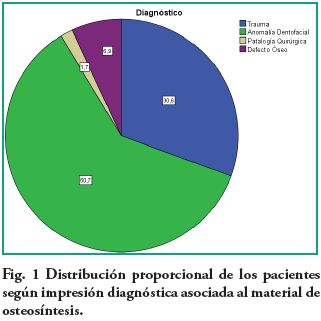

Al analizar la distribución de las impresiones diagnósticas asociadas a material de osteosíntesis (fig. 1), se encuentra que la población estudiada, tiene el doble de imágenes compatibles con cirugía ortognática con respecto a trauma.

El análisis por diagnóstico presuntivo, mostró mayor frecuencia de imágenes compatibles con anomalía dentofacial 105 (60,7 %) que compatibles con trauma 53 (30,6 %) (p=0,00000002). Con respecto a las imágenes asociadas a impresión diagnóstica de trauma (fig 2), 32 (60,4 %) corresponden al género masculino y 21 (39,6 %) al femenino (p=0,0003). Se calculó una relación de riesgo (Odds Ratio) de 3,42 para los hombres. El grupo de edad entre 21 y 30 años presentó mayor cantidad de trauma con 21 radiografías (39,6 %) y el de menor cantidad fue entre los de 51 y 60 años con 3 pacientes (5,6 %). La distribución anatómica del trauma se resume en la tabla 2.